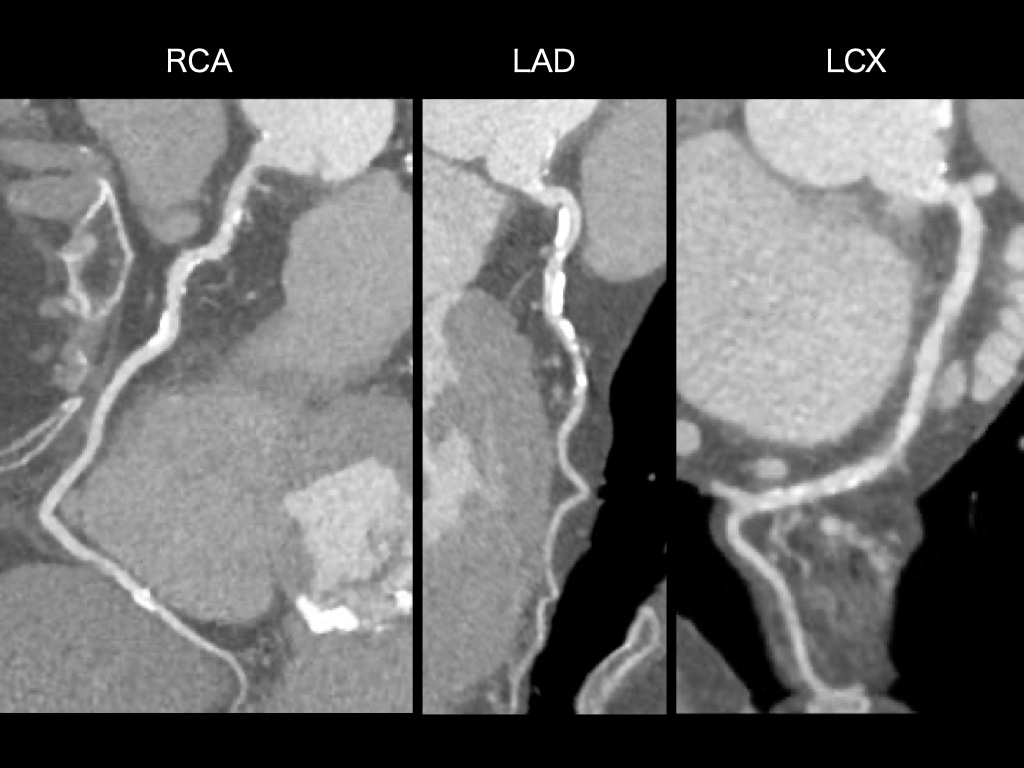

図4.動脈相RCA、LAD、LCX

冠動脈に有意狭窄や動脈硬化性プラークを認めない。